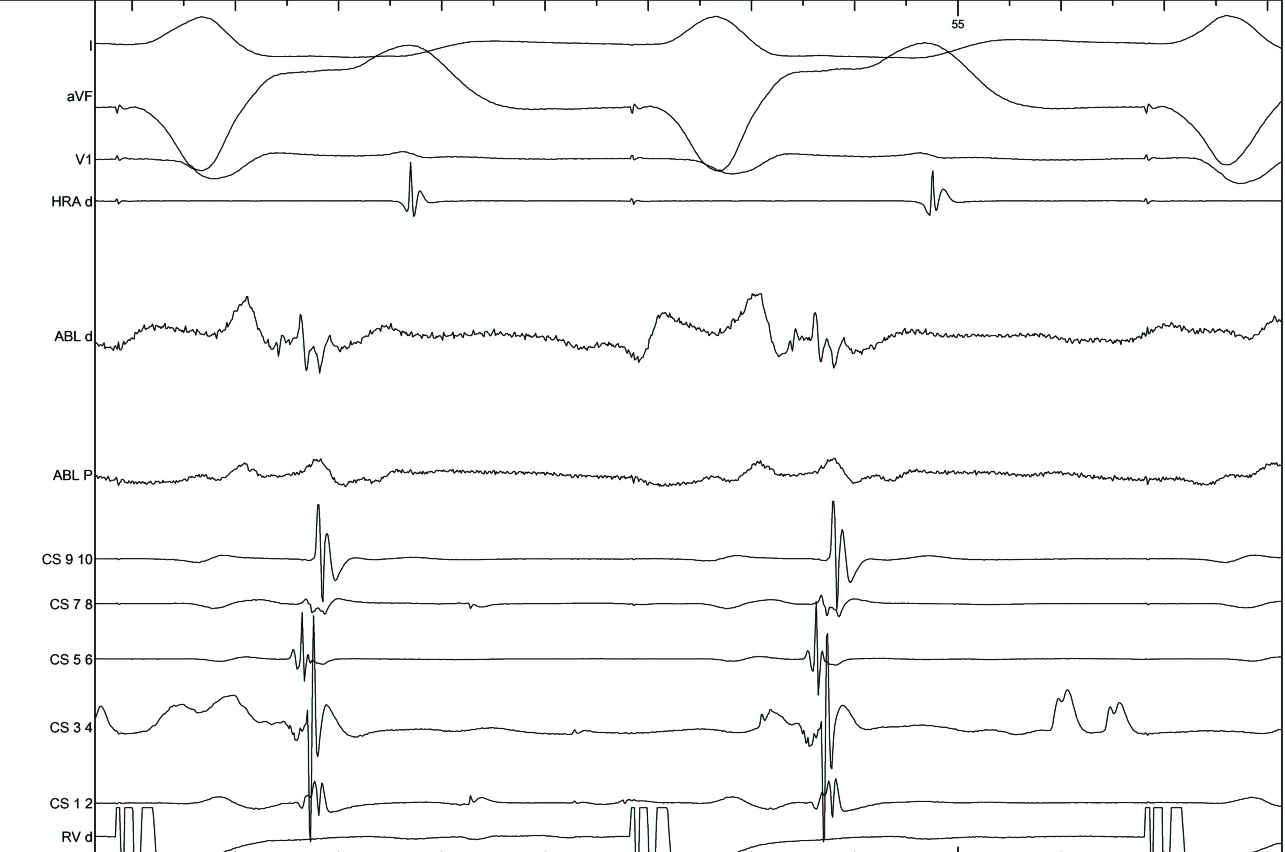

Use triggered mode

trigger.jpg